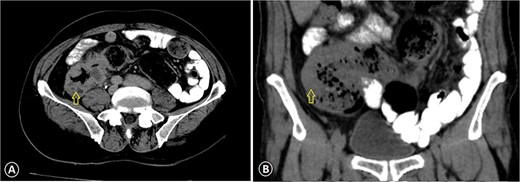

A 68-year-old male admitted for a sternal lump that developed within a few months: (A) lateral view and (B) anterior view.

The patient was diagnosed with stage 3 colon cancer, and the standard of care to be given adjuvant chemotherapy was FOLFOX (leucovorin calcium, fluorouracil, and oxaliplatin) or XELOX (capecitabine ‘Xeloda’ and oxaliplatin). However, the patient has maintained on adjuvant therapy XELODA alone due to its poor performance status with comorbidities. During follow-up after the third cycle of adjuvant XELODA chemotherapy, the patient came with a rapidly enlarging, painful, hard mass on the upper part of his sternum over the last month (Fig. 2). A biopsy of the sternum confirmed metastatic adenocarcinoma consistent with the known primary colon cancer. A CT simulation was done and demonstrated a single destructive lesion in the sternum (Fig. 3). The patient received external beam radiotherapy (EBRT) to the sternum, consisting of 30 Gy delivered in 10 fractions, resulting in symptomatic improvement and a reduction in mass size post-treatment (Fig. 4). The patient was evaluated 3 months after finishing radiotherapy, with a good general condition and resolution of the sternal mass, and he is on a regular follow-up in the radiation oncology clinic.